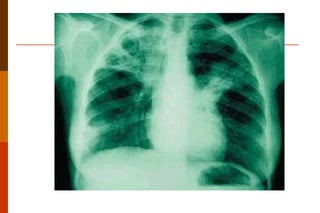

Pneumonia:  É uma infecção do parênquima pulmonar, que pode ser causada por vários microrganismos diferentes, incluindo vírus, bactérias, parasitas ou fungos. Patogenia: o desenvolvimento deste quadro infeccioso passa pela falência dos complexos mecanismos de defesa pulmonar.  Classificações: podem ser classificada sob diferentes aspectos, sendo os mais importantes o etiológico e o anatômico (lobar, lobular ou broncopneumonia e intersticial)

Pneumonia:  Macroscopia Na pneumonia  lobar  o lobo atingido consolida-se de forma homogênea, enquanto as vias aéreas permanecem permeáveis. Na  broncopneumonia  são observados focos múltiplos de infecção, às vezes bilaterais.  Na  pneumonia intersticial  o acometimento pode ser zonal ou difuso, ás vezes de difícil identificação macroscópica.

Pneumonia:  Microscopia: nas formas lobares ou lobulares o ar dos alvéolos é substituído por exsudato inflamatório.  Se não tratada a pneumonia pode evoluir em 4 fases:  inicial ou de congestão  (multiplicação de micro organismos, edema e congestão), hepatização vermelha  (alvéolos ficam cheios de exsudato inflamatório de PMN e hemácias),  hepatização cinzenta  (aumento de leucócitos e da fagocitose pelos macrófagos, fibrina e  diminuição das bactérias)  resolução  (lise de fibrina e diminuição do exsudato).

Pneumonia: MacroscopiaNa pneumonia lobar o lobo atingido consolida-se de forma homogênea, enquanto as vias aéreas permanecem permeáveis. Na broncopneumonia são observados focos múltiplos de infecção, às vezes bilaterais. Na pneumonia intersticial o acometimento pode ser zonal ou difuso, ás vezes de difícil identificação macroscópica.

Pneumonia: Microscopia:nas formas lobares ou lobulares o ar dos alvéolos é substituído por exsudato inflamatório. Se não tratada a pneumonia pode evoluir em 4 fases: inicial ou de congestão (multiplicação de micro organismos, edema e congestão), hepatização vermelha (alvéolos ficam cheios de exsudato inflamatório de PMN e hemácias), hepatização cinzenta (aumento de leucócitos e da fagocitose pelos macrófagos, fibrina e diminuição das bactérias) resolução (lise de fibrina e diminuição do exsudato).